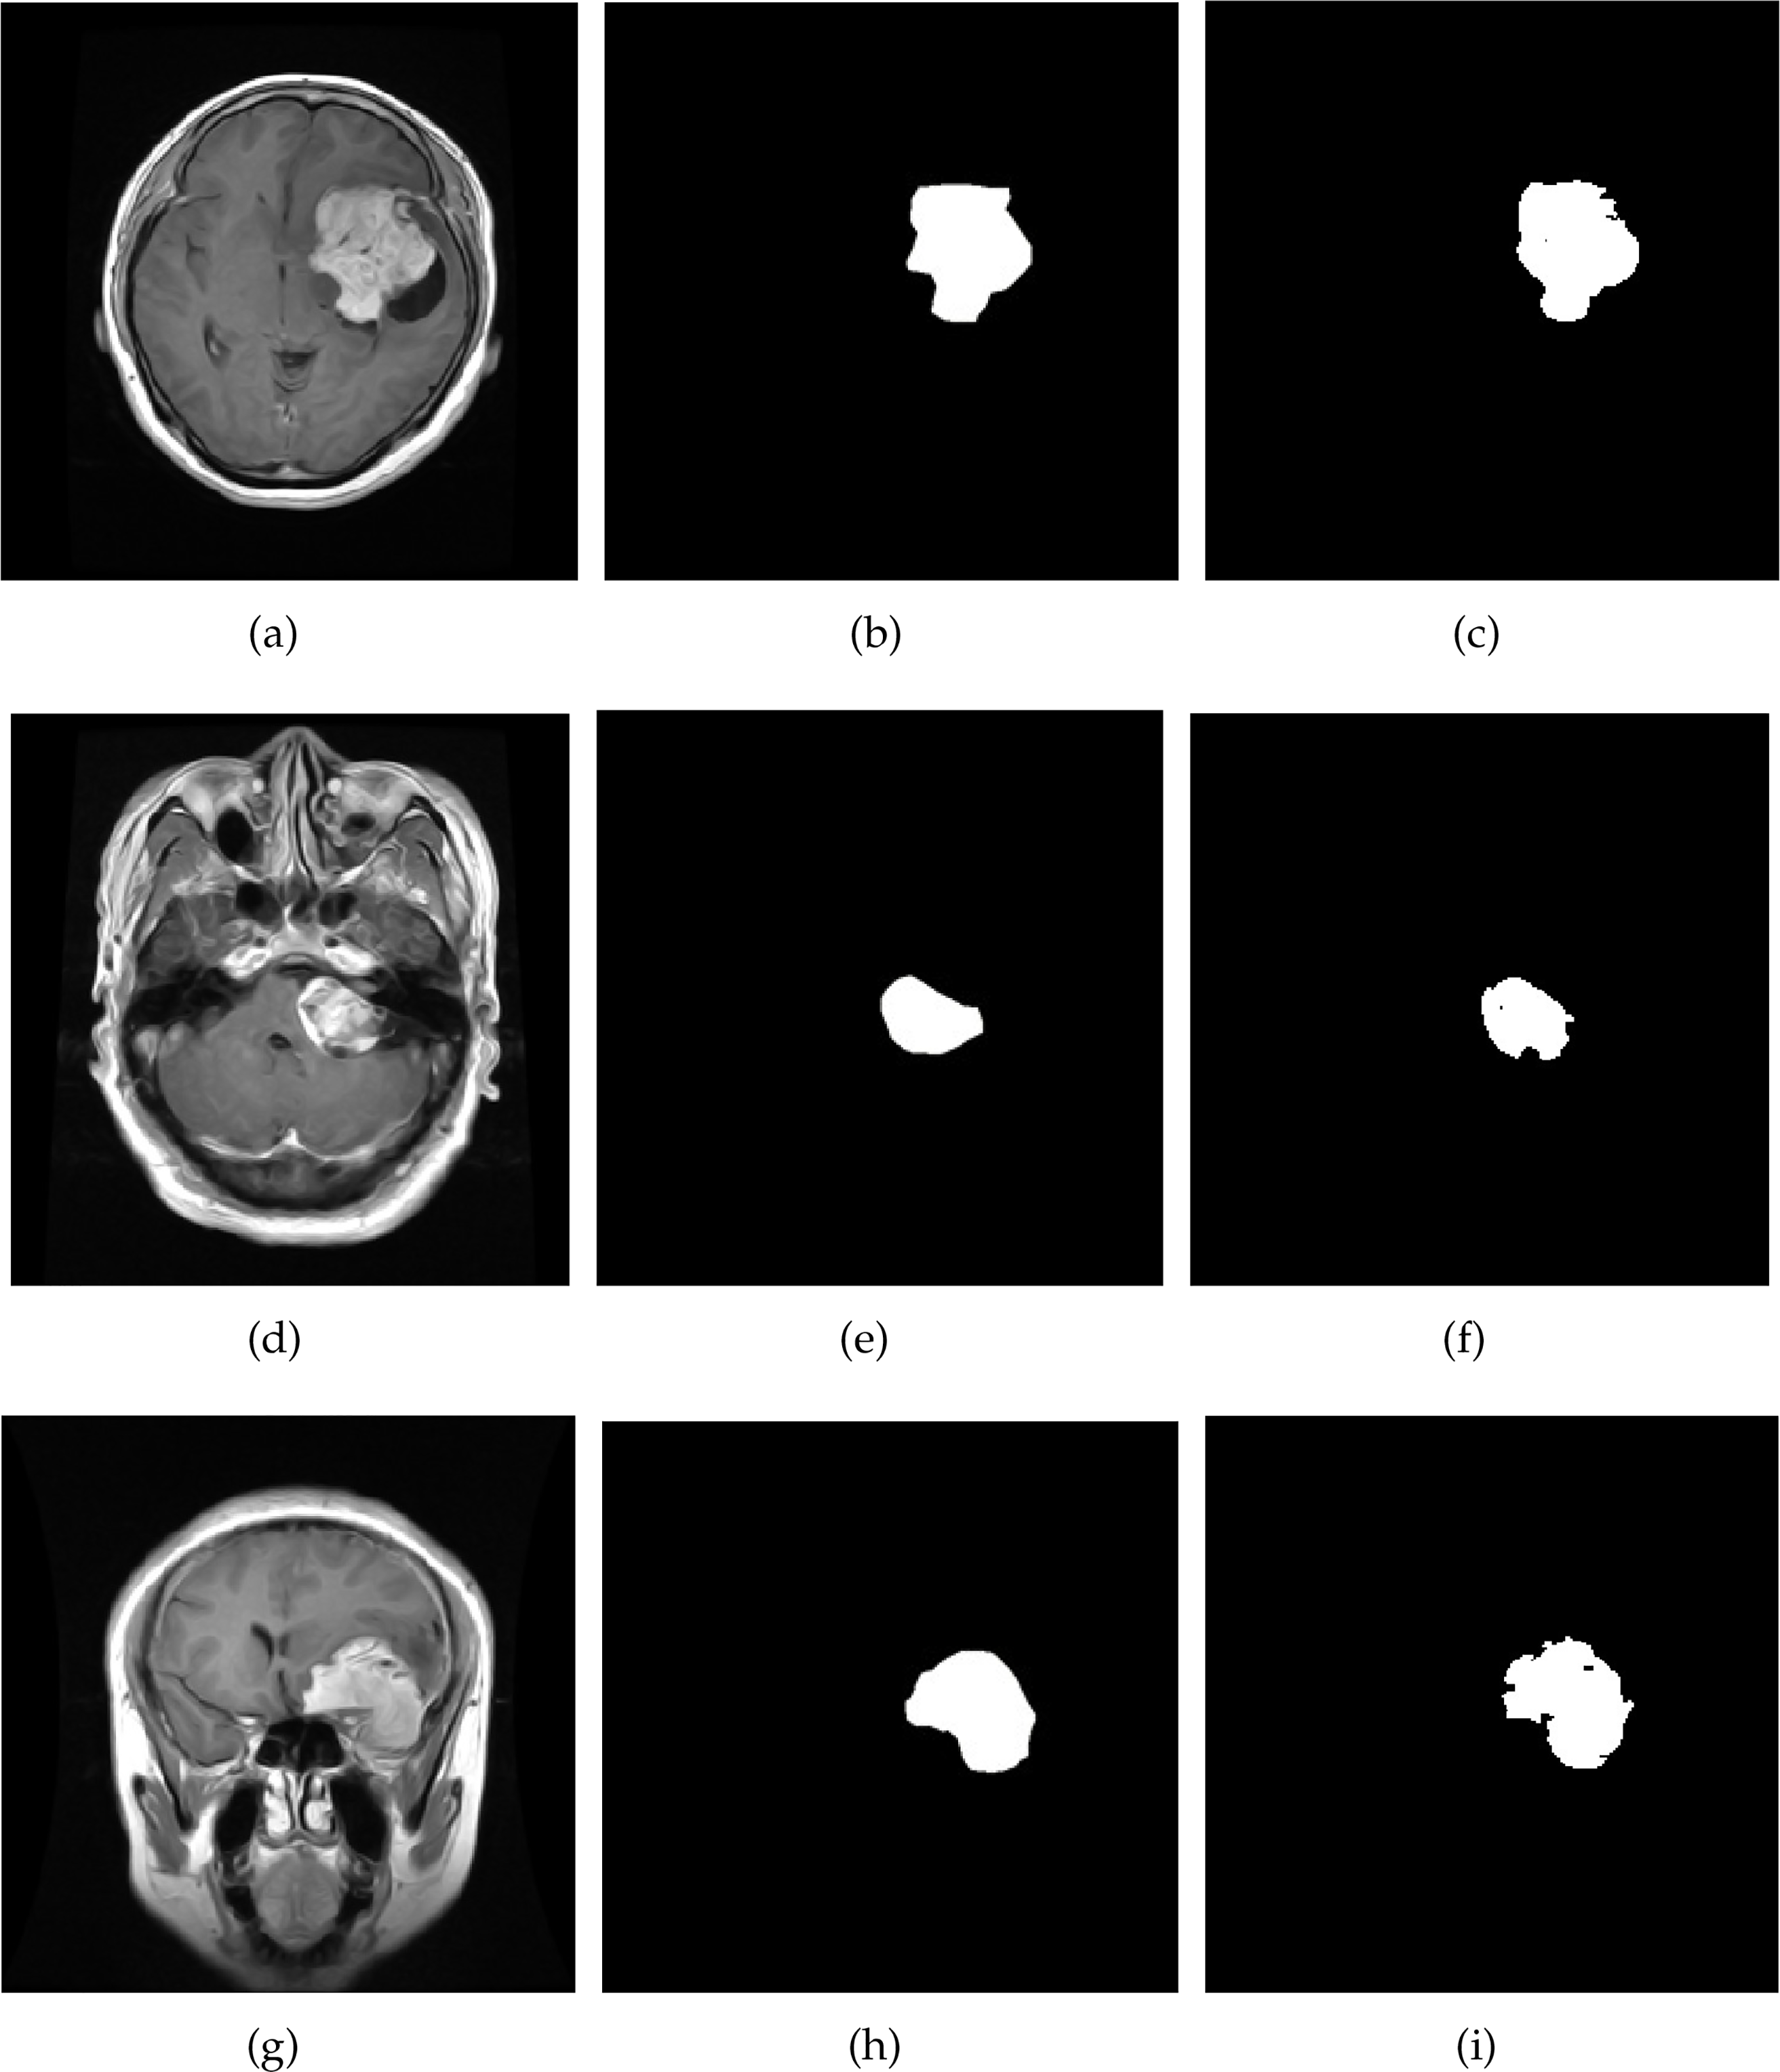

The insightful results presented in Table 4 clearly show the prowess of the proposed approach. The data unequivocally demonstrates that the method efficiently segments brain tumors, yielding highly accurate results. These results are clearly illustrated in Fig. 6, which visually captures the essence of the method’s success in a graphical format. Additionally, the visualization of tumor detections in Fig. 6 provides a clear and compelling demonstration of the module’s remarkable skill in accurately identifying and locating brain tumors. The visual representations testify to the method’s robustness and reliability in real-world scenarios.

Figure 6: Result of brain tumor segmentation using the proposed technique on brain MRI images. The initial column illustrates the images derived from the original dataset, the second column describes the ground truth, and the third column presents the image result

These tangible results collectively underscore the exceptional competence of the module and its promising potential within the domain of brain tumor identification. The results farm the module’s significant contribution to medical image analysis and brain tumor diagnosis by offering substantial and compelling evidence of its capabilities.